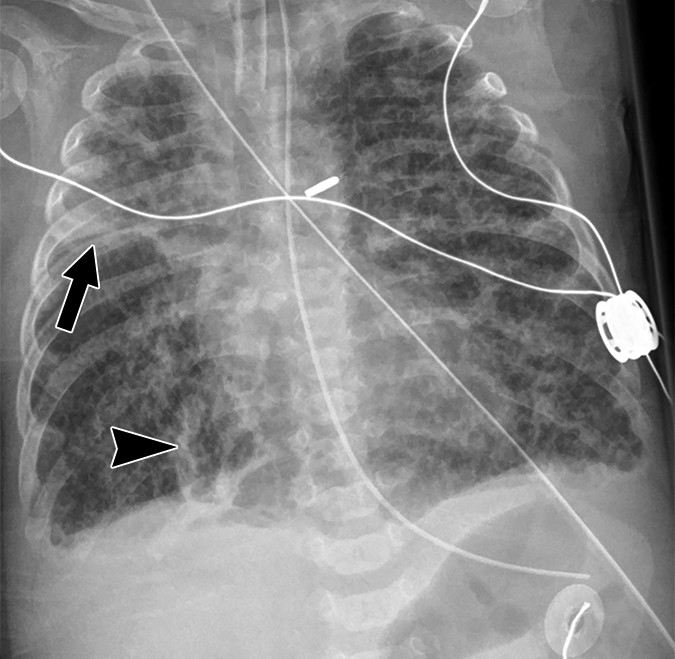

BPD (Bronchopulmonary Dysplasia) Hyperinflation; cystic lucencies; linear fibrotic stranding; heterogeneous opacification Chronic lung disease: oxygen requirement at 28+ days of life; sequela of prolonged ventilation and prematurity

PIE (Pulmonary Interstitial Emphysema) Linear and cystic lucencies radiating from hilum; can be unilateral or bilateral Complication of mechanical ventilation in HMD; air dissects into perivascular and perilymphatic spaces